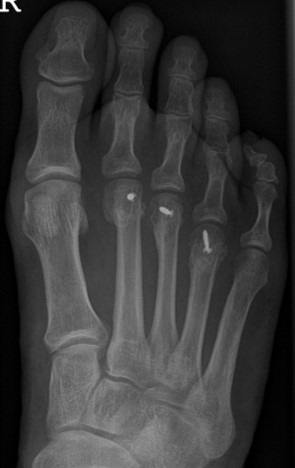

Einerseits kann eine direkte Verkürzung und damit auch Anhebung des Metatarsalköpfchens durch eine Weil-Osteotomie durchgeführt werden. Dabei wird das Grundgelenk des betroffenen Zehenstrahls eröffnet, um den Knochen zehennahe durchtrennen zu können.

Die Weil-Osteotomie kann in minimalinvasiver Technik nur über Minischnitte (Stichinzisionen) durchgeführt werden. Die minimalinvasive Operationsmethode bedeutet ein sehr weichteilschonendes Verfahren, was sich in einer geringeren Schwellneigung und einem niedrigeren postoperativen Schmerzniveau äußert.